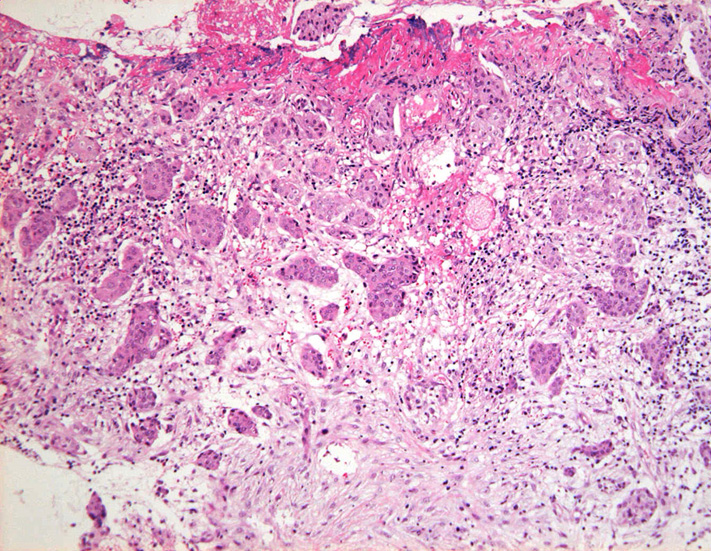

S状結腸粘膜生検組織所見:

粘膜筋板直下に小型胞巣を作って浸潤し炎症性の間質をともなう。 浸潤性増殖のわりに細胞は均一, そんなに異型性も強くない。apoptosisに陥った細胞が散在する。部位によっては胞巣状増殖細胞は細胞間橋がありそうな扁平上皮様に見える。深いところは線維性間質が増えてきて細胞は索状となりcarcinoidなども鑑別候補となるかもしれない。明らかな腺管形成, 粘液産生はみられない。35歳男性, わりとおとなしい扁平上皮癌様の組織か?と生検初見時に考えられた。desmoplasticな間質にもよく観察するとバラけた細胞異型が認められる。 (腫瘍胞巣①, ③)

腫瘍胞巣①腫瘍胞巣②腫瘍胞巣③深い部分